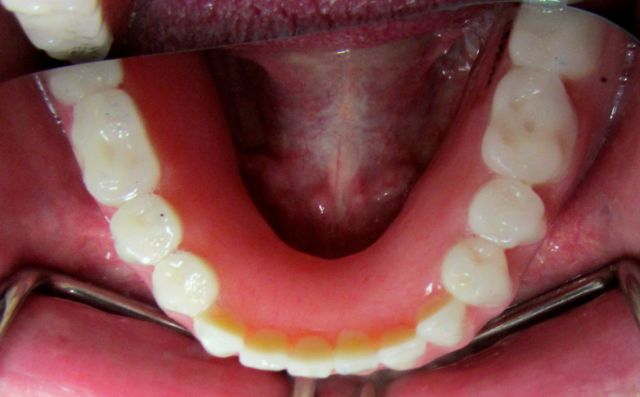

Looking at the lower arch, we had Mike chew on articulating paper, to check on where his denture is chewing.